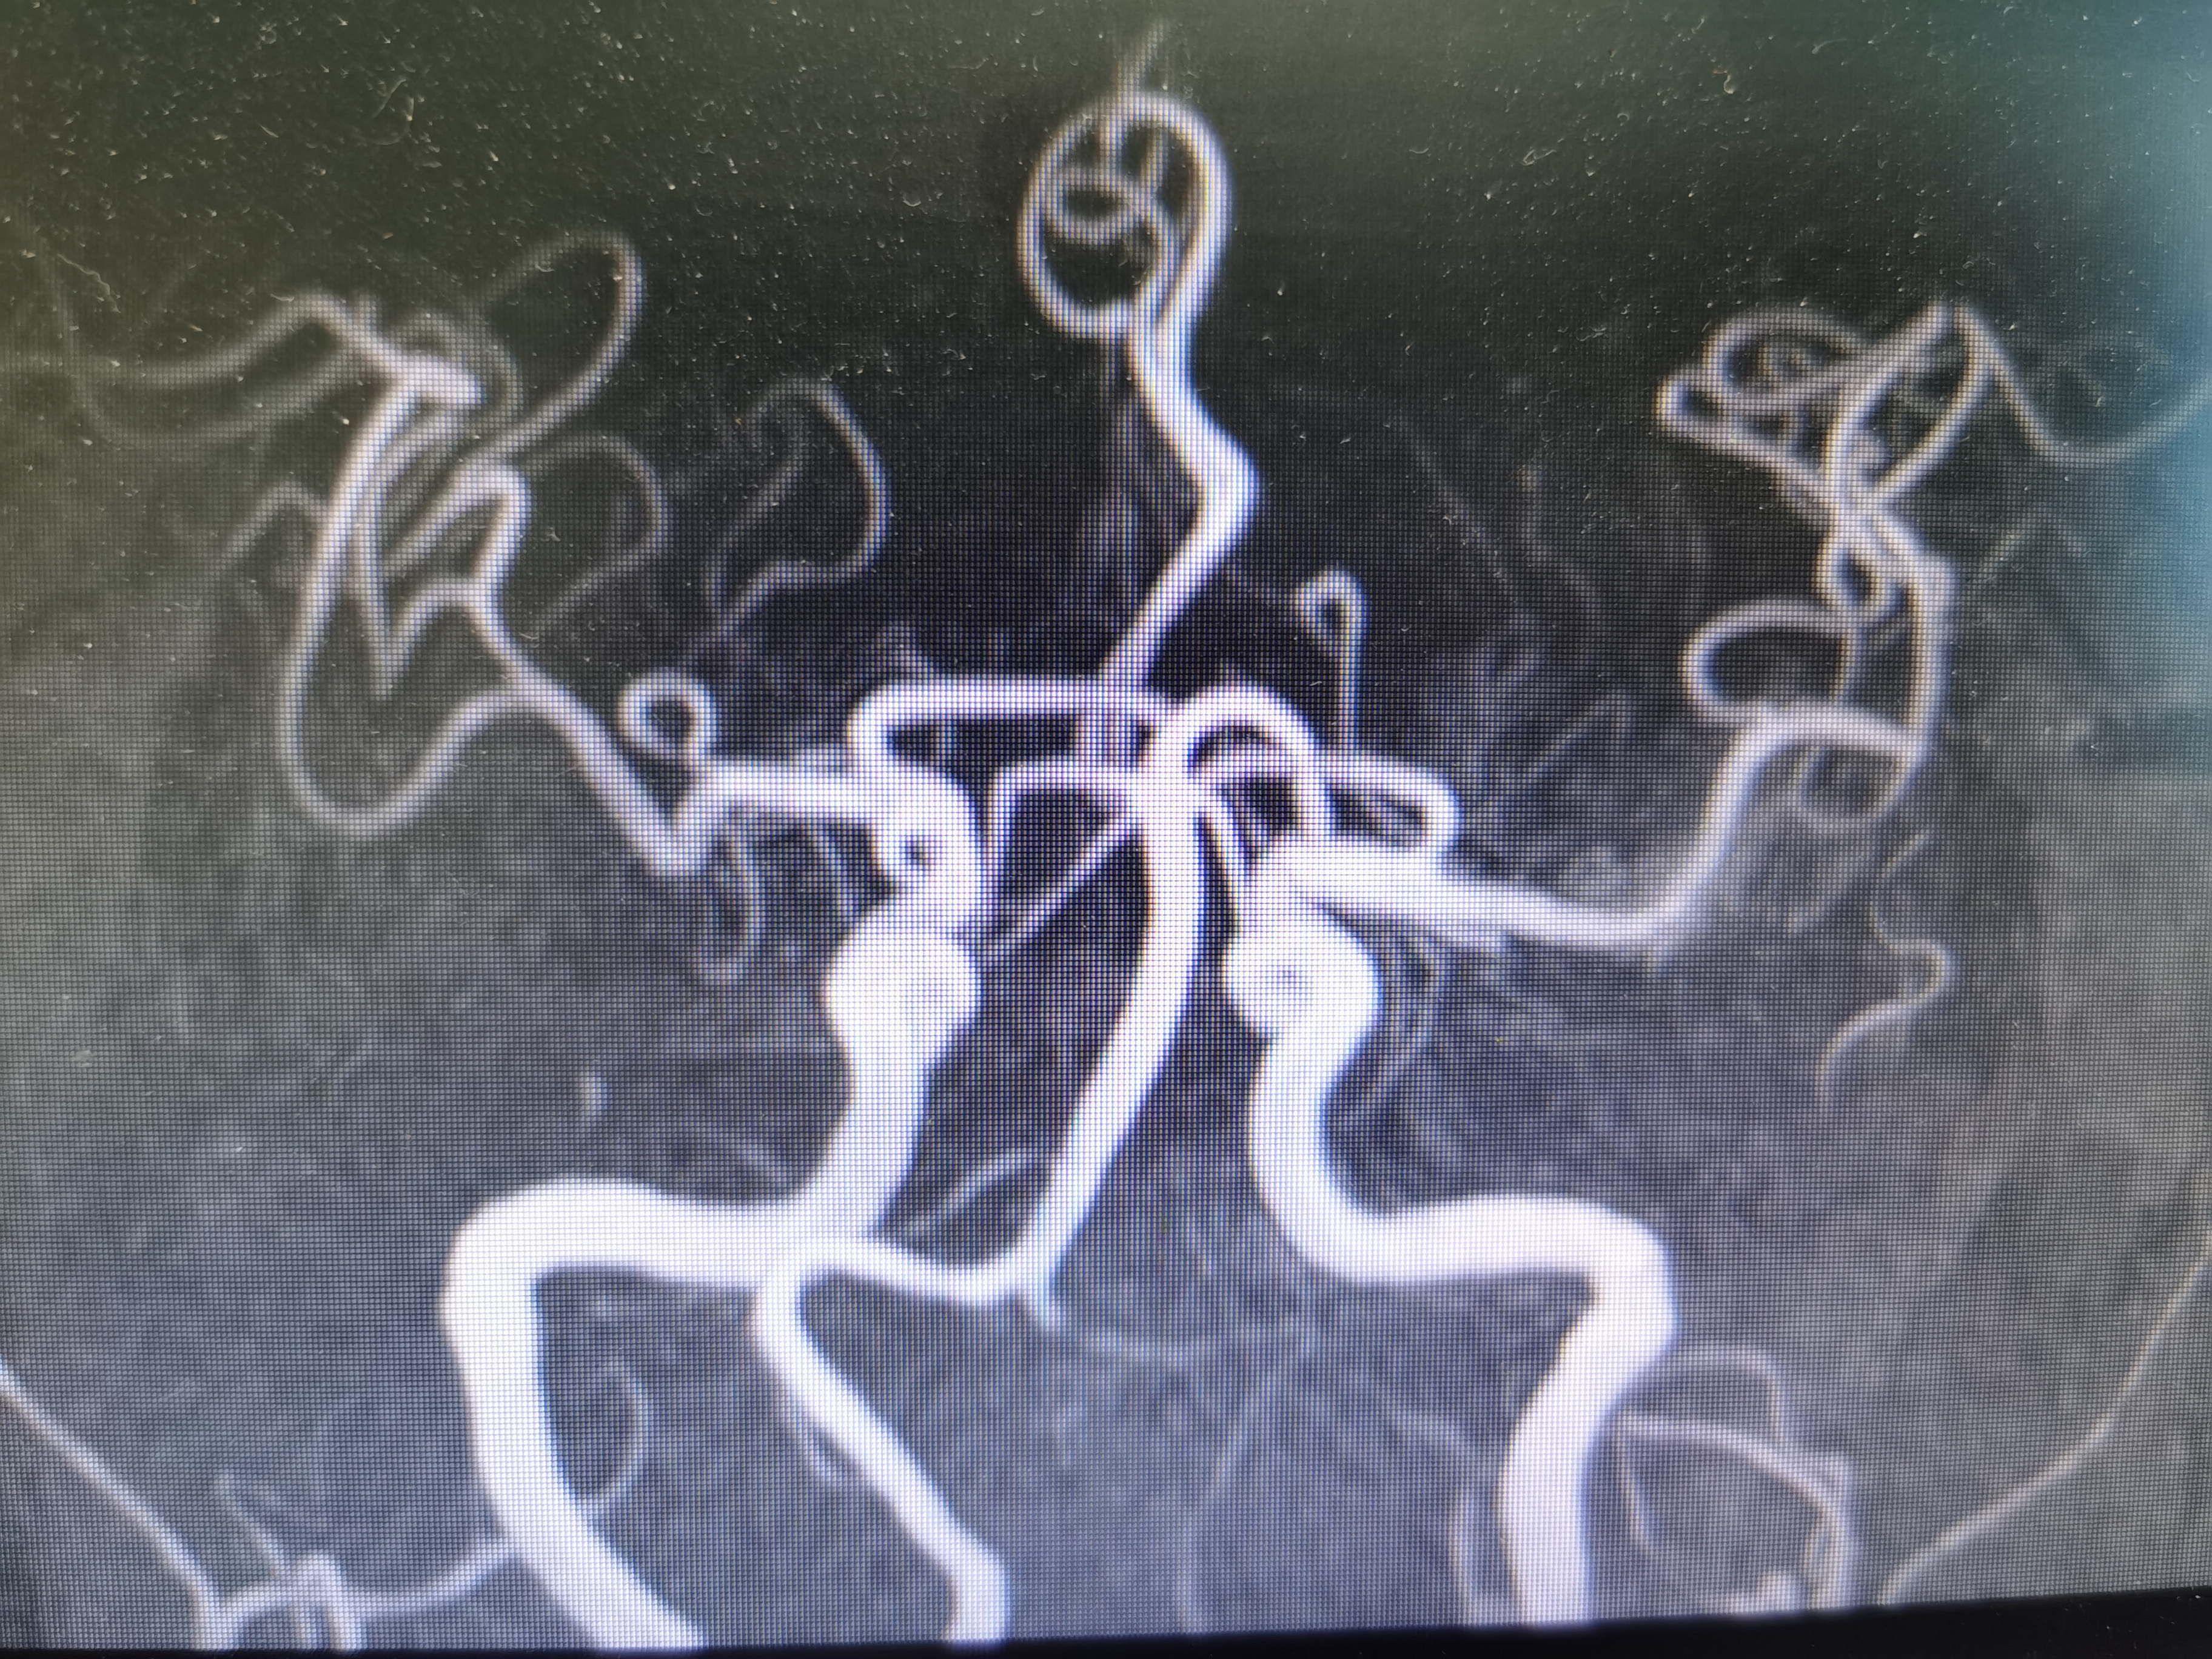

2、CTA证实左椎动脉起始部重度狭窄合并血栓,系责任血管,存在急性闭塞或残存血栓脱落至基底动脉风险,需积极处理。

3、手术过程中,先用小球囊扩张病变,观察血栓情况,及时应用支架全程覆盖血栓及病变部位,成形满意。